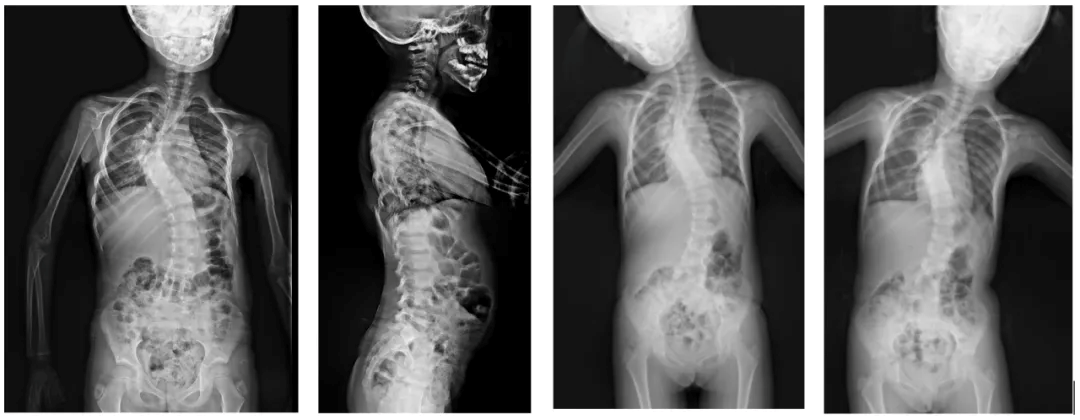

Preoperative imaging examination

2019-05-05: consistent with scoliosis deformity

1. Full-length spine film consistent with scoliosis deformity

3. CT of thoracic spine showing scoliosis

(1) May 10, 2019, growth rod implantation, pre- and post-operative comparisons

Preoperative → growth rod implantation → full-length piece orthotopic after 6 adjustments